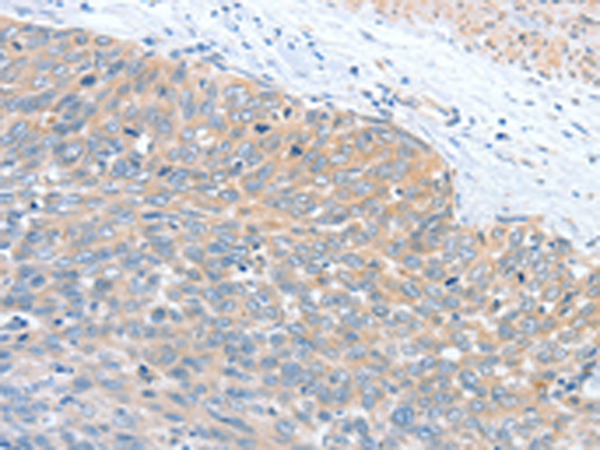

分类: 科研抗体货号: P08176别名: PLA2G4; cPLA2-alpha应用: IHC反应种属: Human, Mouse, Rat